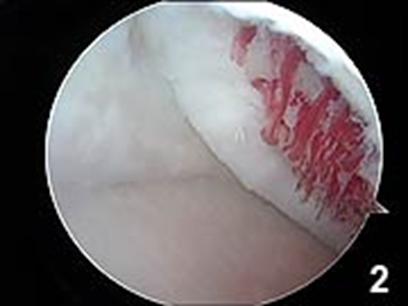

Chirurgul trebuie sa fie foarte atent atunci cand examineaza posteriorul condililor femurali. Daca se semnaleaza orice vatamare/rana/deteriorare pe suprafetele articulare, trebuie sa se cerceteze atent calitatea cartilagiului. Orice flapsuri instabile sunt inlaturate prin folosirea unui aparat de ras electric artroscopic sau curette. Apoi, un curette este folosit pentru a debrida stratul de cartilagiu calcifiat de la baza in toata grosimea defectului. Acest pas se bazeaza pe activitatea lui Frisbi, care a demonstrat vindecarea suprafetei articulare superioare la un cal, cand stratul cartilagiului calcifiat este indepartat. Cand indepartam stratul cartilagiului calcifiat, in general nu se foloseste un aparat de ras. Cu un aparat de ras este dificil de controlat cantitatea de os eliminat, si este posibil ca osul subcondral sa fie afectat.

Dupa indepartarea cu succes a stratului de cartilaj calcifiat, o andrea este folosita pentru a face mai multe gauri mici (mirofracturi) in osul expus al defectului condral aflate la distanta de 1-2 mm. Trebuie lasata o punte de oase potrivita intre gauri. Tehnica de microfracturi are numeroase avantaje fata de foraj. Mai intai de toate, creaza o leziune termala mai mica. Mai mult, cu microfracturi, chirurgul este capabil sa intre in zonele dificile ale suprafetei articulare cu un control mai bun asupra adancimii de patrundere. La finalizarea microfracturii, o suprafata aspra este generata pentru a aderenta cheagului de sange care contine celule mezenchimale nediferentiate de la osul subcondral. Trebuie avut grija ca cele mai marginase parti ale leziuni sa fie patrunse de andrea pentru a ajuta la vindecarea tesutului reparator la imprejmuirea suprafetei articulare. Odata ce microfractura este finalizata, pompa artroscopica este oprita pentru a se asigura ca sangerarea maduvei curge din gaurile mici umpland defectul.[54]